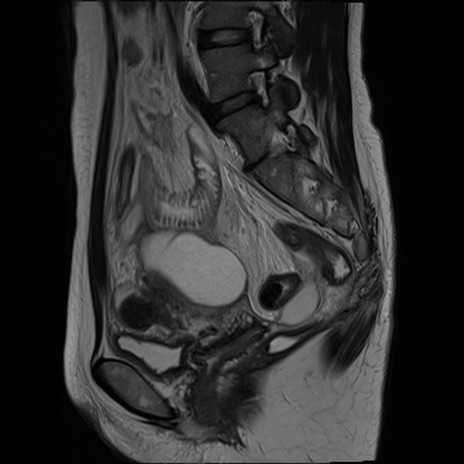

症例39 T2WI(矢状断像)

MRI(4日後)